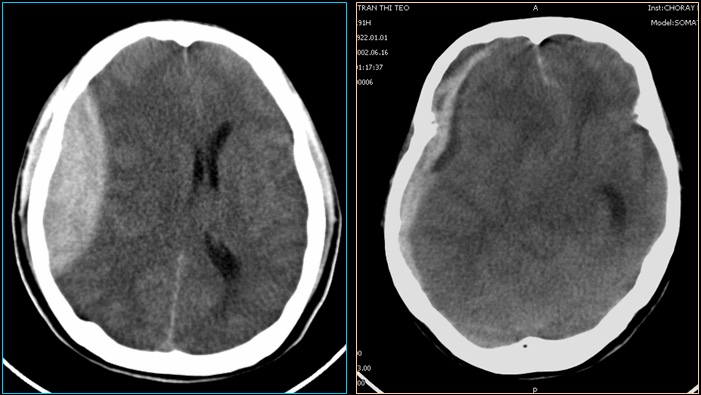

Hình 2: Máu tụ ngoài màng cứng và dưới màng cứng